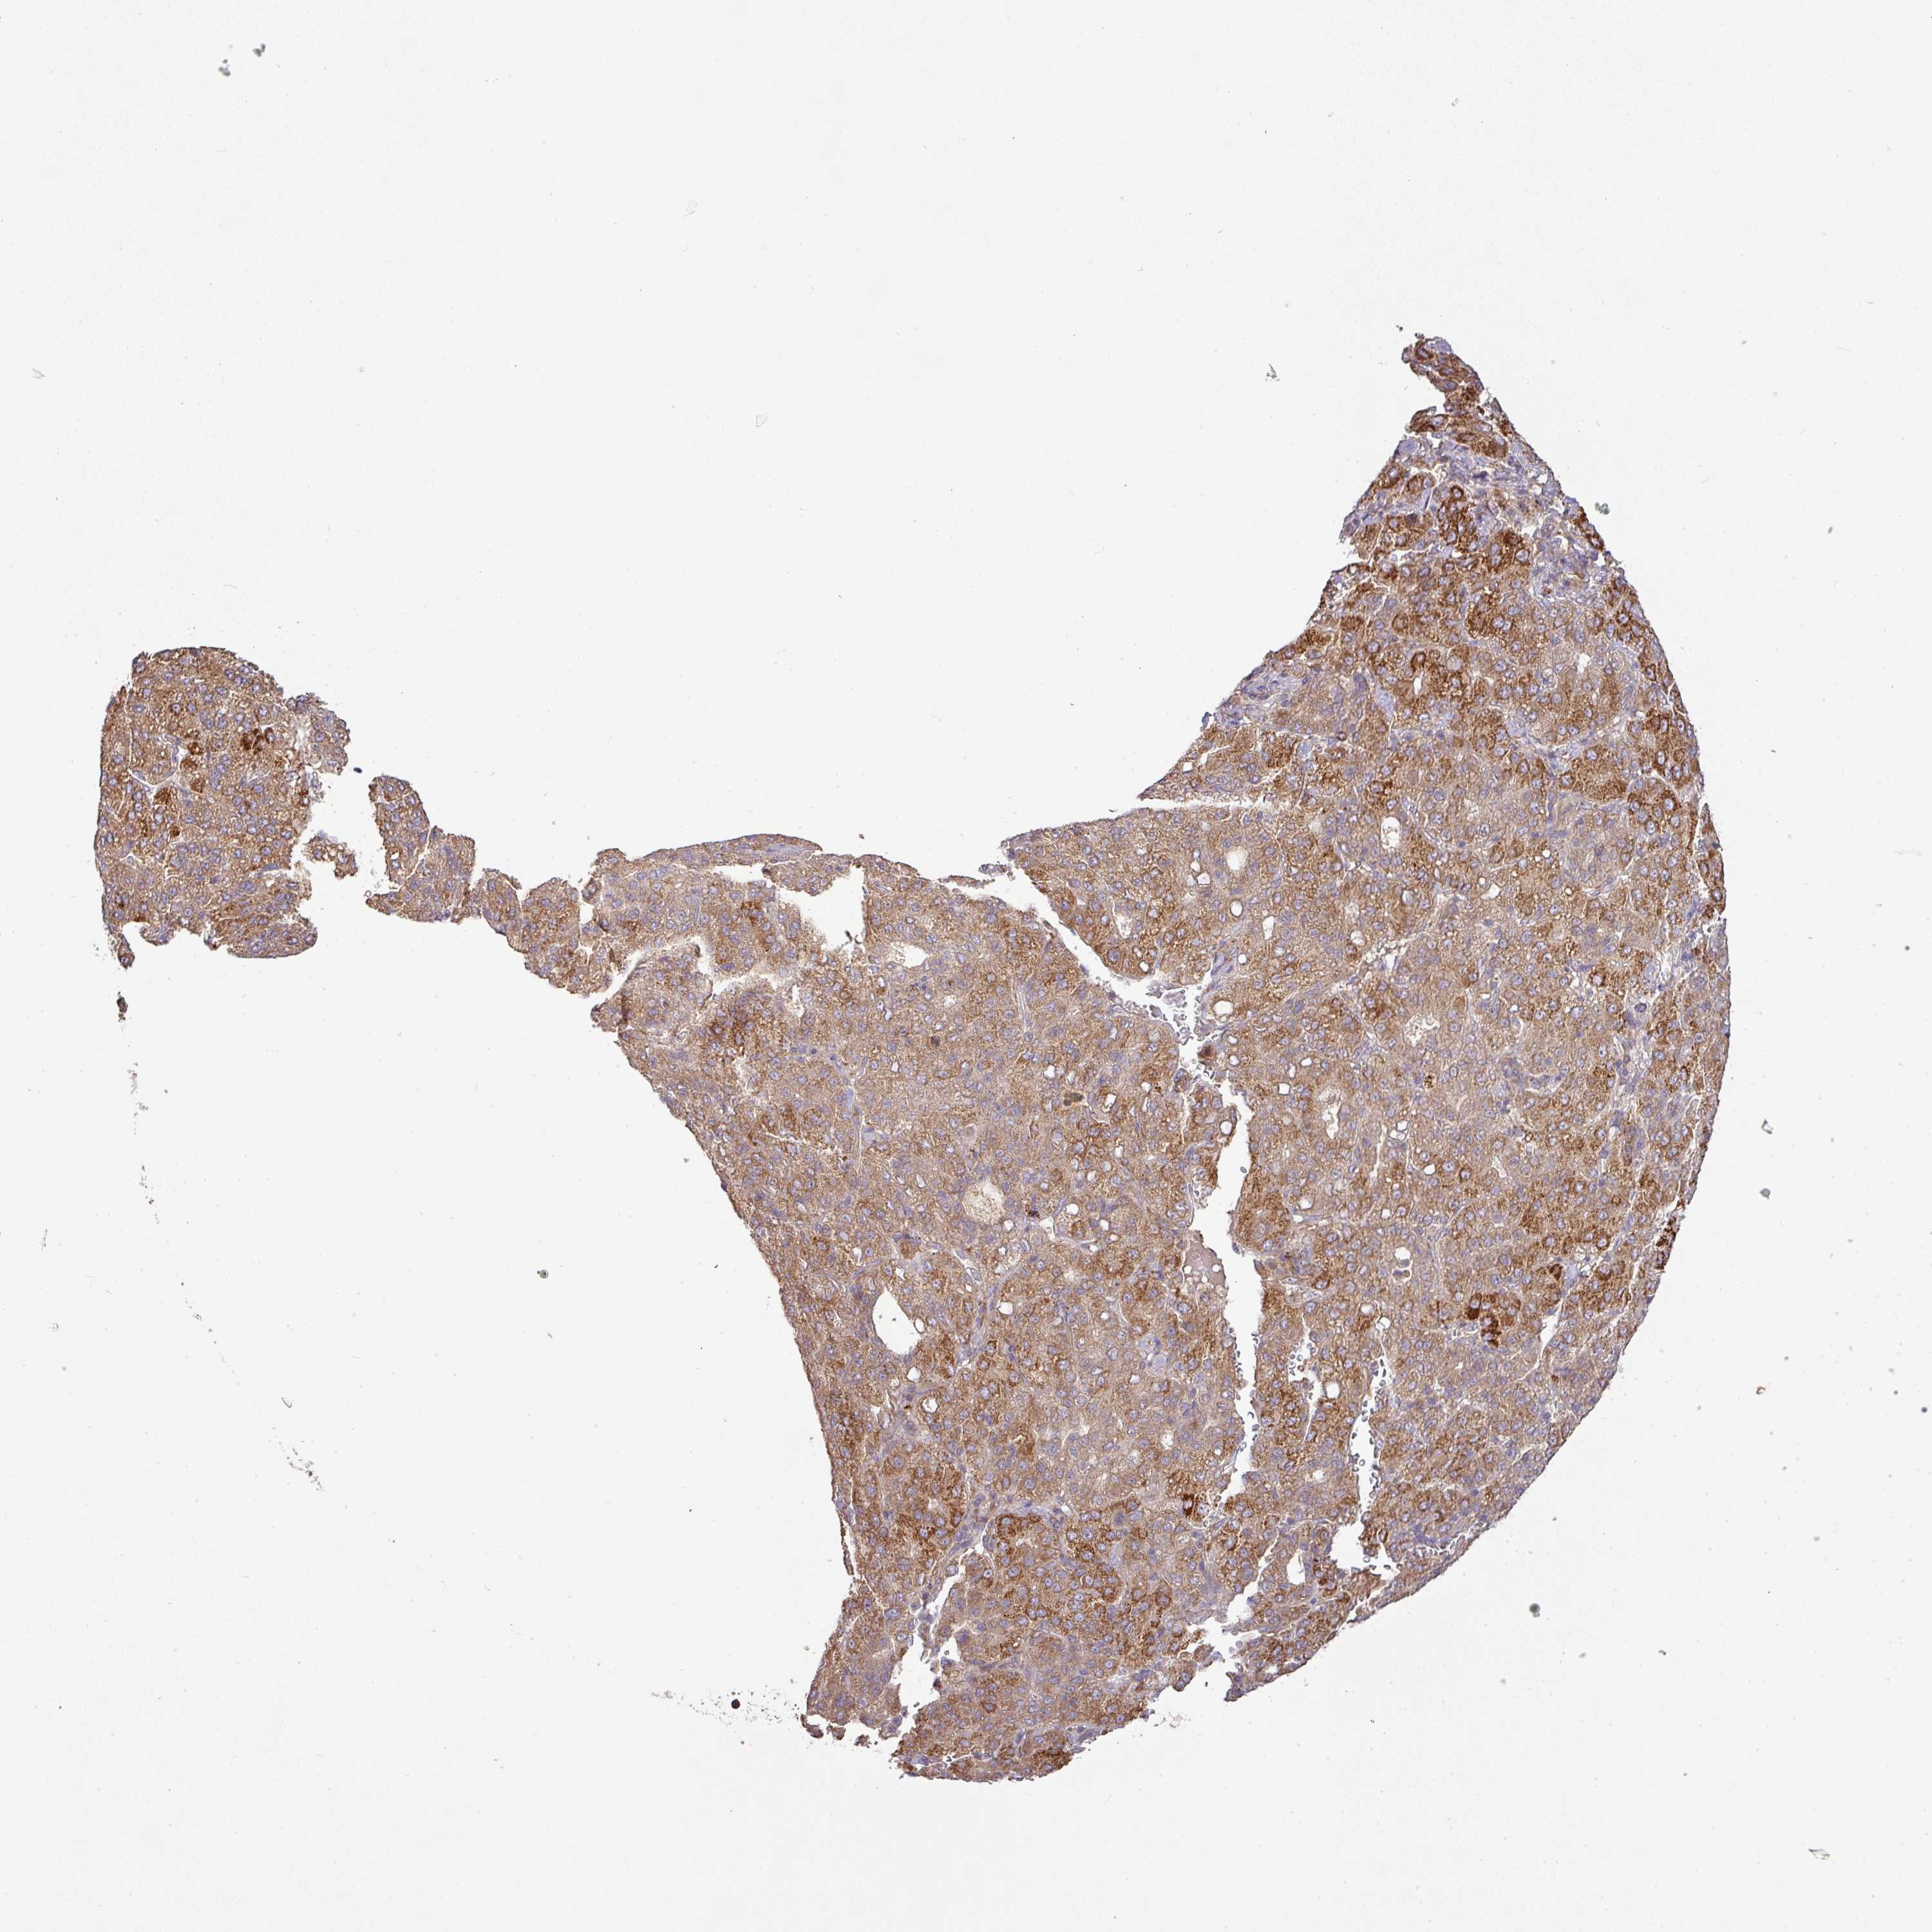

LIVER CANCER - Protein expressioni

A mouse-over function shows sample information and annotation data. Click on an image to view it in a full screen mode. Samples can be filtered based on level of antibody staining by selecting one or several of the following categories: high, medium, low and not detected. The assay and annotation is described here.

Note that samples used for immunohistochemistry by the Human Protein Atlas do not correspond to samples in the TCGA dataset.

Antibody stainingi

Antibody staining in the annotated cell types in the current human tissue is reported as not detected, low, medium, or high, based on conventional immunohistochemistry profiling in selected tissues. This score is based on the combination of the staining intensity and fraction of stained cells.

Each image is clickable and will lead to virtual microscopy that enables deeper exploration of all samples and also displays staining intensity scores, fraction scores and subcellular localization as well as patient and tissue information for each sample.

Antibody HPA053938

Staining

High

Medium

Low

Not detected

Intensity

Strong

Moderate

Weak

Negative

Quantity

>75%

75%-25%

<25%

None

Location

Nuclear

Cytoplasmic/membranous

Cytoplasmic/membranous,nuclear

Carcinoma, Hepatocellular, NOS

Cholangiocarcinoma